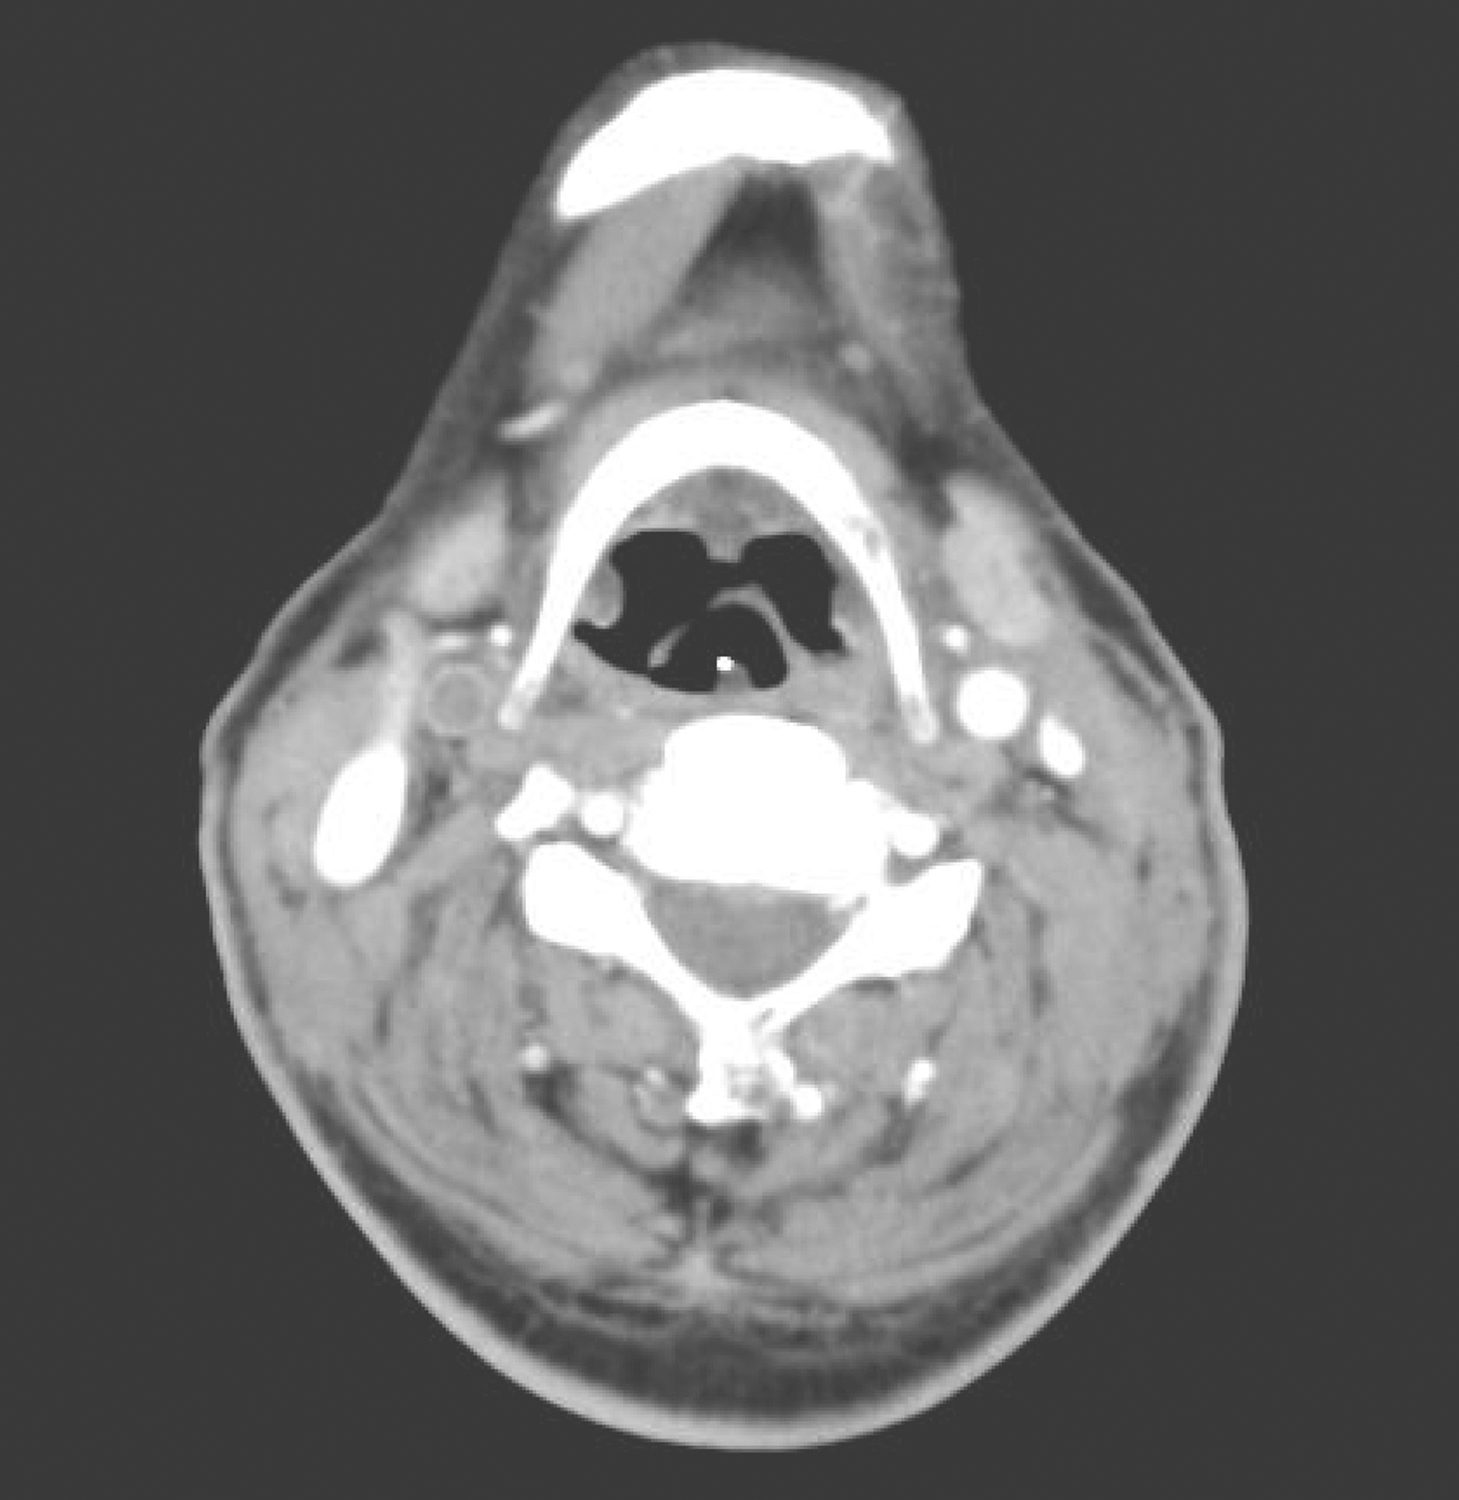

8.2013年8月20日颈胸部CT:参阅2013年6月1日术前CT图像。

(1)甲状腺术后,术区未见明确异常强化结节或肿物;气管切开术后,双侧颈部清扫术后改变,颈前皮肤略增厚,皮下多发索条影,双侧胸锁乳突肌密度不均匀,边界不清楚,考虑术后改变,请随诊。右颈总动脉内可见栓子形成(图6)

图6 颈部增强CT示右颈总动脉内栓子形成